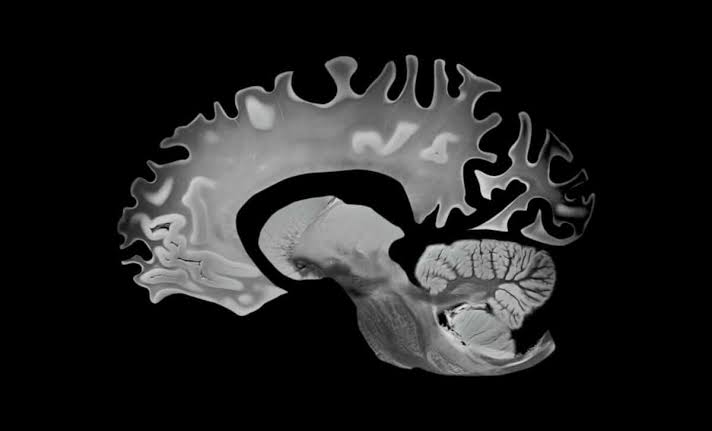

This “Hybrid” Diet Doesn’t Just Protect Your Heart, It’s Slowing Brain Aging Too

A decade-long study of 1600 adults just revealed a diet that measurably slows brain aging. The findings may change everything.